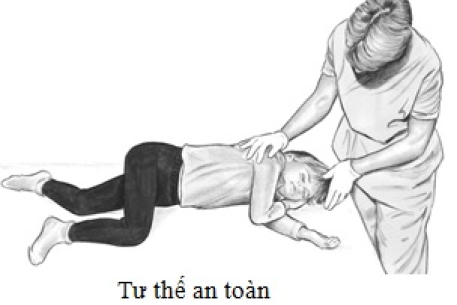

Cách phòng chống và sơ cứu đúng cách khi bị đuối nước

Theo Tổ chức Y tế Thế giới (WHO), trong thập kỷ vừa qua đuối nước đã cướp đi sinh mạng của hơn 2,5 triệu người. Đây cũng là một trong những nguyên nhân hàng đầu gây tử vong trẻ em từ 5-14 tuổi trên thế giới. Hơn 90% các trường hợp đuối nước xảy ra ở các quốc gia có thu nhập thấp và trung bình, đặc biệt ở các vùng nông thôn.